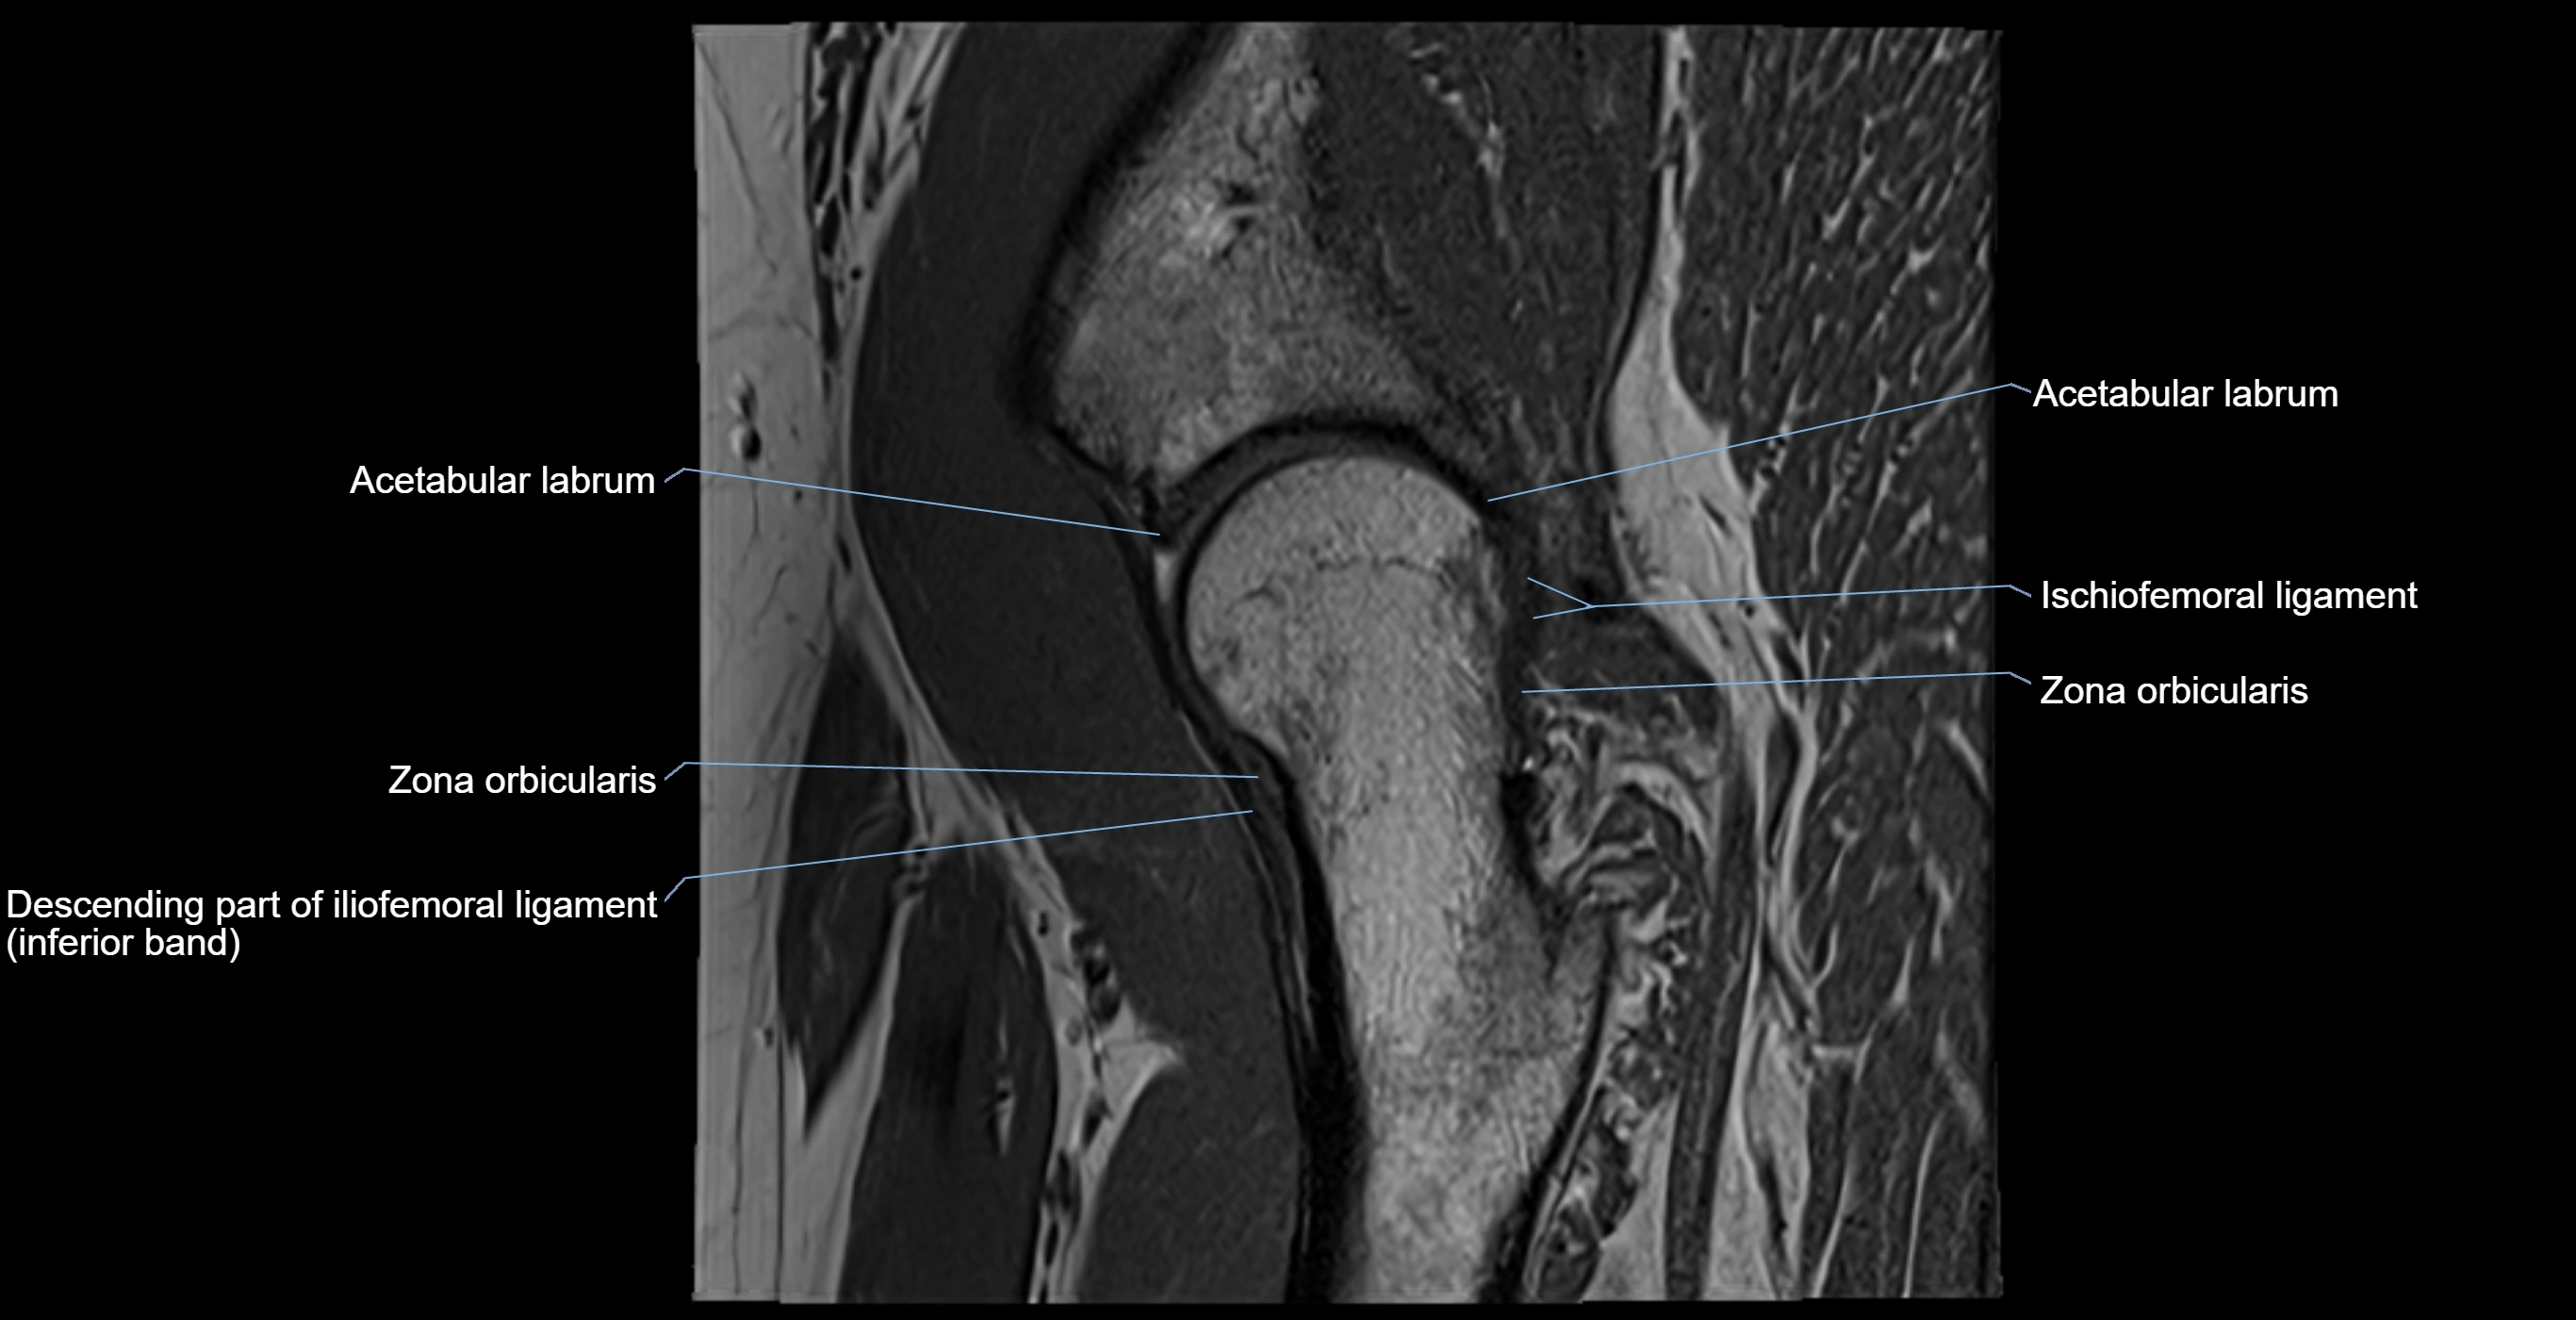

MRI Appearance

T1-weighted images:

• Labrum: low signal intensity (dark)

• Surrounded by intermediate signal joint fluid (bright on arthrogram)

• Tears: linear or focal areas of intermediate-to-high signal interrupting labral continuity

T2-weighted images:

• Joint fluid: bright, making labral tears visible as fluid extending into or around labrum

• Degeneration: may show areas of increased signal within labrum

MRI image

image